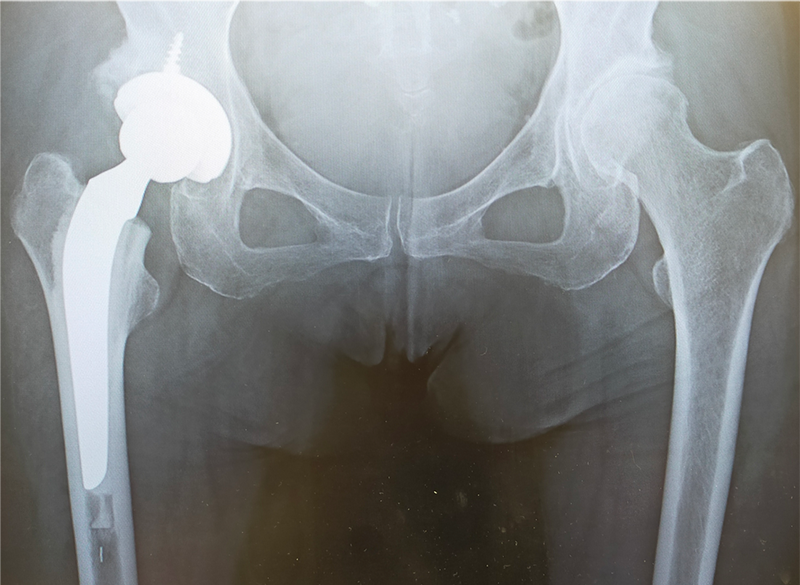

〈手術後のレントゲン〉(正面)

〈手術後のレントゲン〉(側面)

当院にて両側の人工股関節全置換術(THA)を施行。アプローチはAMIS(前方最小侵襲手術)で行い、術中に神経ブロックを併用することで、術後の疼痛コントロールを行い、術翌日から離床、リハビリを進めることができました。術後すぐに歩けることに本人も驚いていました。また、術後は一切の肢位の制限も行っていません。